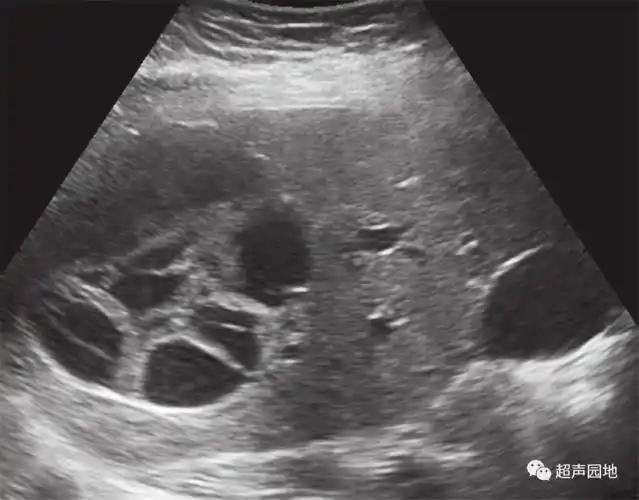

各式各样的肝囊肿,你都见过吗?